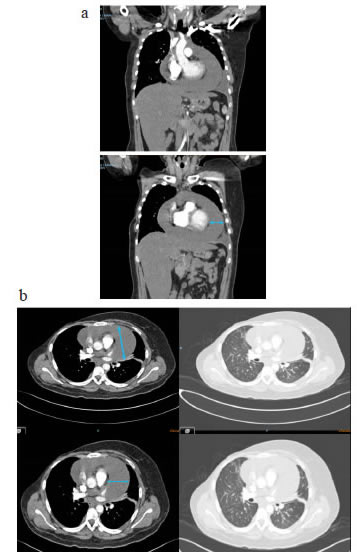

En el electrocardiograma se encontraron signos de bajo voltaje y ausencia de la onda p. En la radiografía de tórax se observó ensanchamiento de la silueta cardiomediastínica y borramiento del ángulo costofrénico izquierdo (figura 1). En la tomografía de tórax (TC), se observó un derrame pericárdico con separación de 3,5 cm entre las hojas del pericardio y un derrame pleural izquierdo (figura 2).

Después de la quimioterapia, en la tomografía por emisión de positrones (PET-CT) se observaron los implantes pleurales, con engrosamiento pleural y pericárdico, y derrame pericárdico. Hubo progresión según los criterios de reacción por PET-CT (Positron Emission Tomography Response Criteria, PERCIST). No se observaron signos de taponamiento cardiaco (figura 6).

En la radiografía de tórax se observó derrame pleural izquierdo y aumento del tamaño de la silueta cardiomediastínica (figura 9).En la TC de tórax se apreciaba derrame pericárdico, con tabiques, derrame pleural izquierdo, y engrosamiento pleural y pericárdico (figura 10).